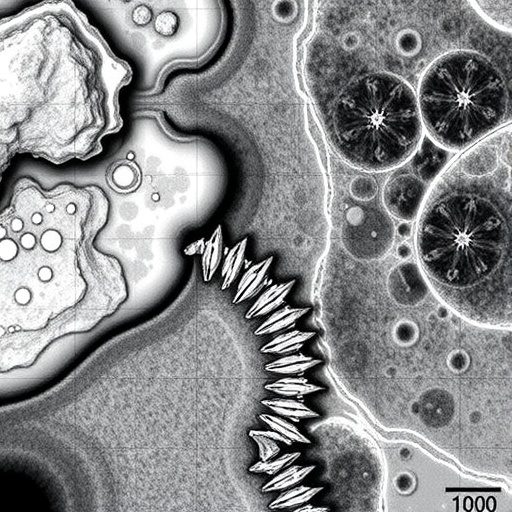

At the core of this breakthrough lies a fusion of advanced imaging modalities with sophisticated computational analysis. Through the integration of these modalities, the research team has been able to extract detailed fiber orientation and density information directly from histological samples in their native state. This capability not only preserves the integrity of the tissue but also ensures that the resulting data reflect authentic biological configurations, providing a vital tool for accurate assessments.

The researchers employed cutting-edge imaging hardware capable of capturing fine structural details at the micron scale. The resulting image data underwent rigorous computational processing, wherein algorithms meticulously analyzed fiber orientations, lengths, and intersections within the tissue matrix. This analytical procedure not only mapped fibers with remarkable accuracy but also allowed quantification of fiber properties that could be critical in understanding tissue mechanics and pathology.

Moreover, this method could serve as a vital complement to existing imaging techniques, such as multiphoton microscopy or electron microscopy, by offering a rapid and less intrusive assessment tool. Its compatibility with a broad range of tissue types—including soft and hard tissues—enhances its applicability across domains such as neuroscience, oncology, and regenerative medicine. The ability to obtain highly detailed fiber maps from untouched samples accelerates hypothesis generation and validation in these fields.